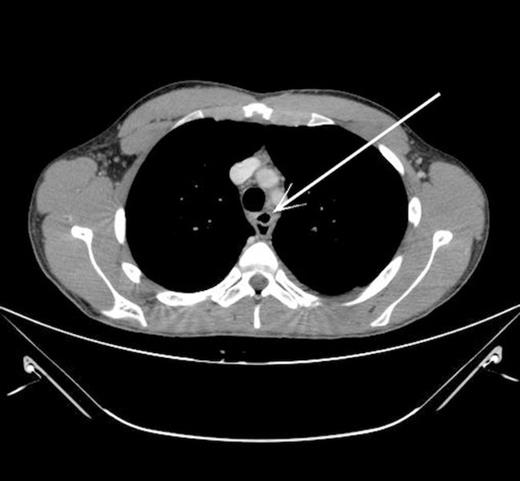

The Surgeons were contacted and a CT thorax and abdomen was requested. A CT thorax and abdomen showed a small (7mm x 5mm) air pocket anterior to the oesophagus in keeping with an isolated perforation. There was no evidence of pneumothorax, pneumomediastinum or fluid collection (Fig. 3).

CT thorax showing pocket of air anterior to oesophagus (indicated by arrow)